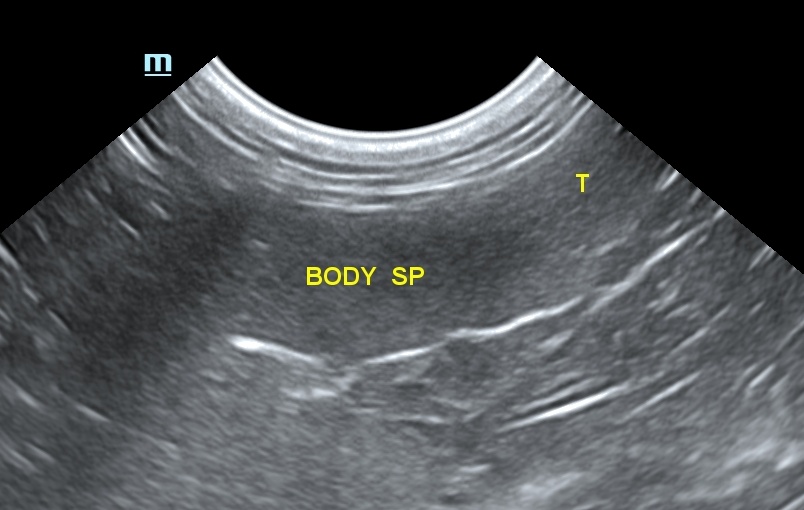

스캔 시 비장의 모양은 혀(tongue) 모양을 가지며, 꼬리부분이 머리 부분과 몸통보다 넓습니다. 횡단면은 삼각형 모양으로 개의 비장보다 작으며, 위치가 일정합니다. 비장의 머리 부분은 위비장 인대에 의해서 위에 고정되어 있으며, 몸통과 꼬리는 많은 유동성이 있으나, 그 유동성의 정도는 개보다 적습니다. 건강한 고양이에서 비장은 얇고, 고에코성의 캡슐표면으로 부드러운 모양으로 잘 확인이 되며, 깨끗한 경계 부위를 가집니다. 비장의 실질은 치밀하고 동질성의 미세한 과립성의 echotexture를 가집니다(그림 2).

비장의 측정에서 가장 신뢰할 만한 것은 비장의 머리부분을 재는 것이었습니다. 그러나 최근 권장된 최종 프로토콜에는 혈관이 내장 표면에 보일 때 횡단면에서 비장의 근위 1/3 높이를 측정하는 것을 추천합니다.4) 이때 5.1~9.1mm가 되며, 9.1mm 초과 시에는 비장의 비대를 뜻합니다(표 1).